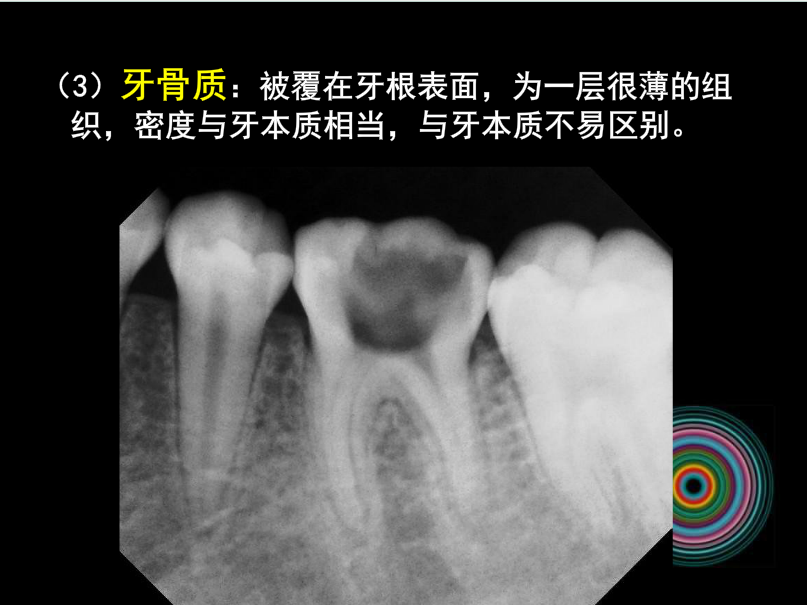

口腔頜面外科 影像技術(shù)